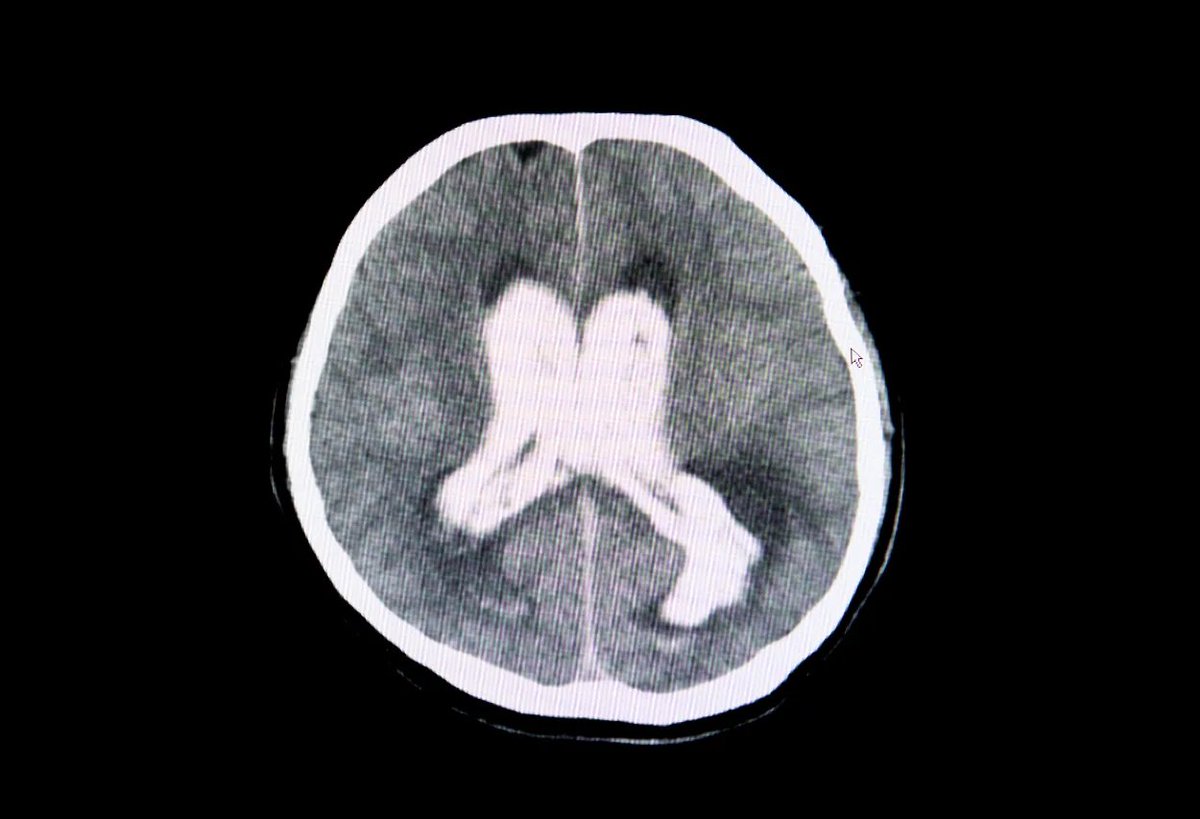

@MidwesternDoc Patients with severe head trauma and dangerously high brain pressure saw their pressure drop within minutes of IV DMSO.

CT scans confirmed swelling reduced.

Many went from near death to minimal or no impairment. Image